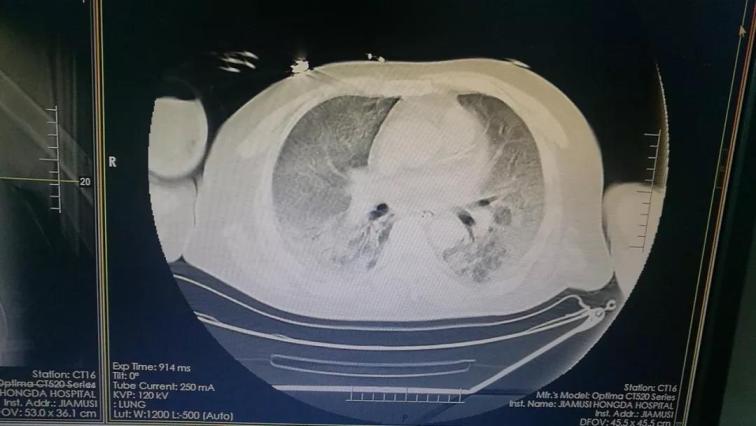

5月15日佳木斯大學(xué)宏大醫(yī)院重癥醫(yī)學(xué)科(ICU)收治1例急性上呼吸道重癥感染的患者。該患者繼往有腎病綜合征病史,在鶴崗市三甲醫(yī)院診斷為頑固性ARDS。CT片顯示雙肺透過(guò)度減低,并見(jiàn)大片高密度影,部分病灶實(shí)變,其中可見(jiàn)支氣管氣相,俗稱“大白肺”。當(dāng)?shù)蒯t(yī)院認(rèn)為此患者已經(jīng)沒(méi)有搶救價(jià)值了。